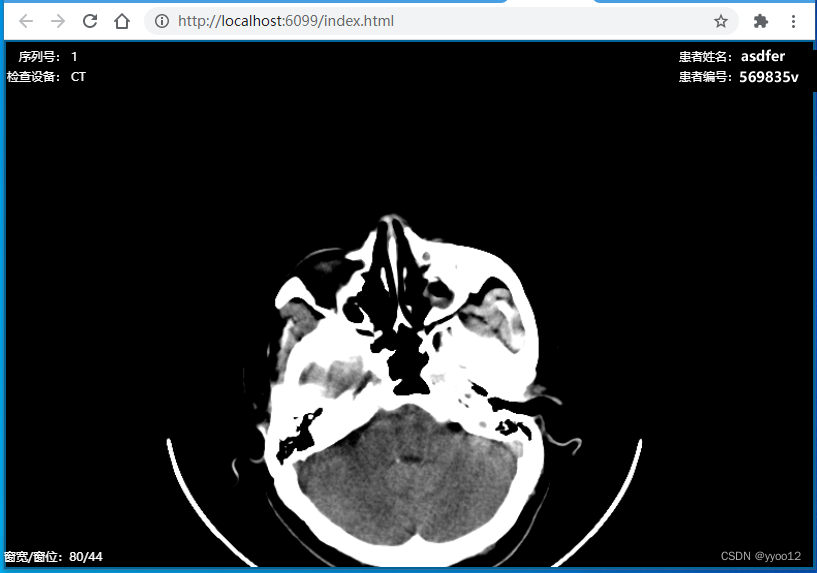

医疗影像dicom在线浏览,翻页、窗宽窗位、缩放、测量、CT值等,js直接加载文件流,整合cornerstone .js 、dicomParser.js、imageLoader.js,翻页时加载,几百张影像流畅,结合医卡,无网时本地离线使用